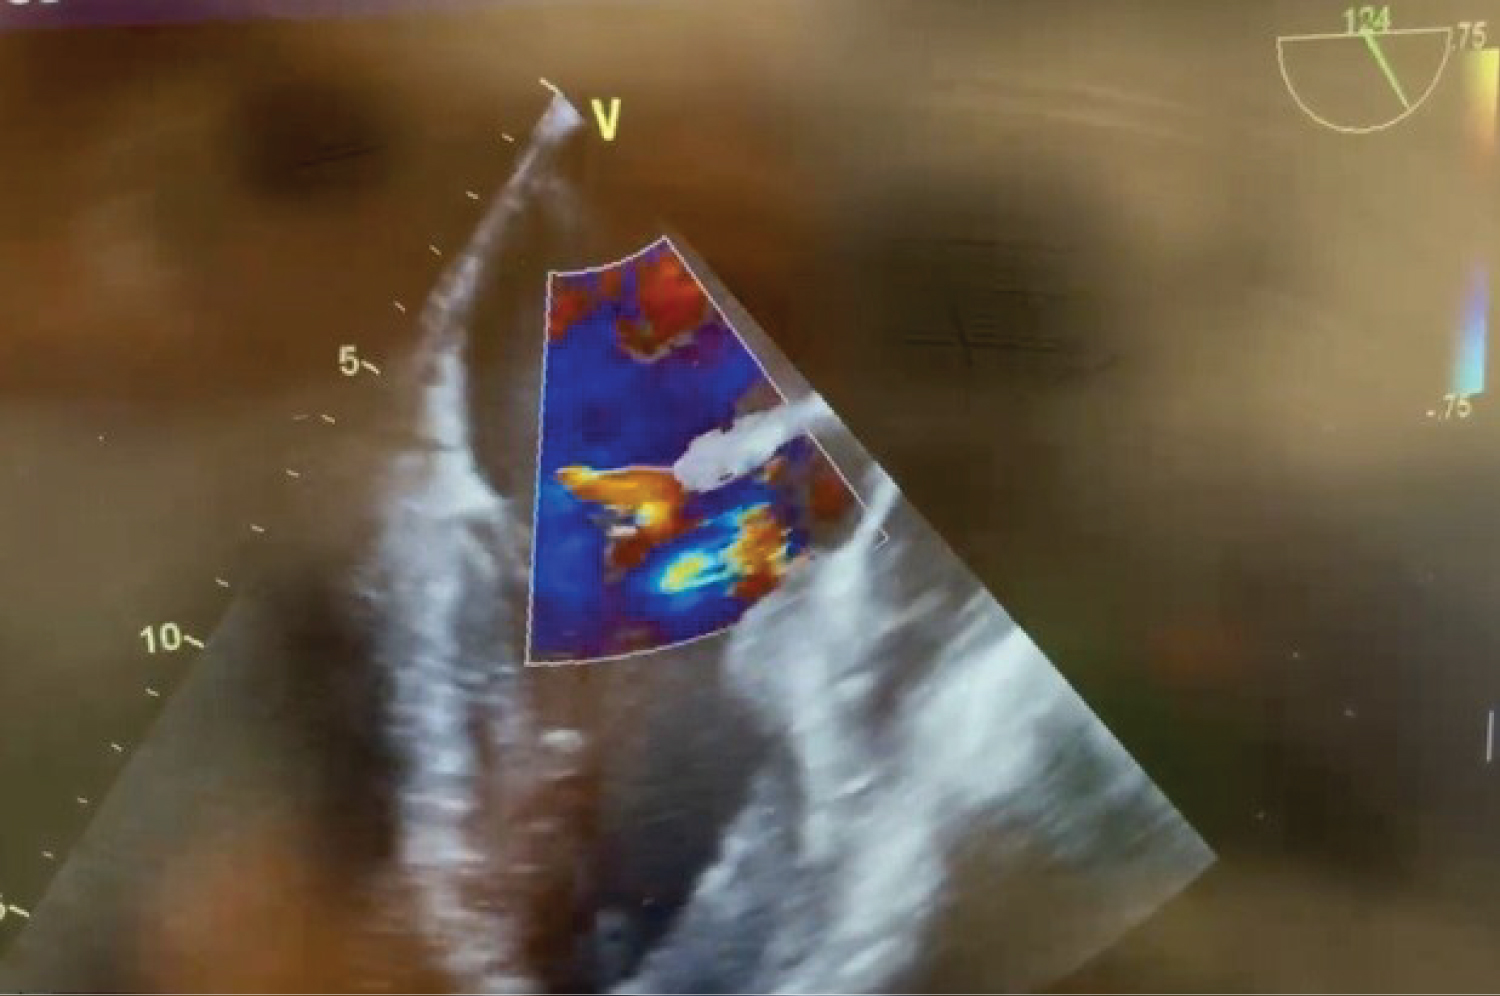

After an uneventful induction of anesthesia and placement of lines, a pre-bypass TEE confirms the presence of the A2 vegetation (Figure 1) and perforation with severe MR (Figure 2). The patient is also found to have moderate AI (Figure 3) and a patent foramen ovale (PFO) with left to right shunting (Figure 4). The surgeons are informed of the new findings and plans are made to close the PFO and to inspect the aortic valve. Aortotomy is made, and the aortic valve is found to have redundant tissue. Both the aortic and mitral valves are replaced with mechanical St. Jude's valves. The PFO is closed with a single suture, followed by de-airing of the heart under TEE guidance and weaning from CPB.

Figure 4: Pre-bypass TEE midesophageal long axis view illustrating mitral and aortic insufficiency. View Figure 4